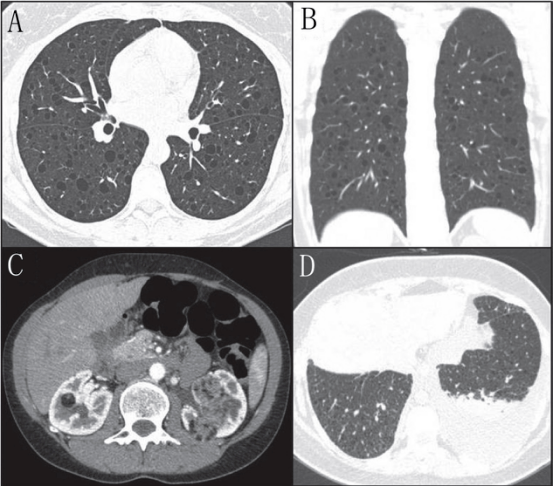

淋巴管平滑肌瘤病(LAM)是一种低度恶性肿瘤,最常发生育龄期妇女;LAM的特征是气道、血管和淋巴管周围不典型平滑肌细胞(LAM细胞)的增殖;LAM可以是一种独立的疾病,或与结节性硬化综合征有关,是由结节性硬化症1或2个基因突变引起的(7.8)。LAM最常见的呼吸表现包括运动时进行性呼吸困难和复发性气胸(高达70%的病例),以及较少见的咳嗽、咯血和乳糜胸(8)。LAM的囊肿通常是规则、薄壁的;通常直径为2-10毫米,广泛分布,数量不等,并被正常肺实质包围(图2A和2B)。(9)LAM囊肿的形成推测是由于LAM细胞在远端空腔扩张时阻塞终末细支气管,以及/或由于蛋白酶和蛋白酶抑制剂之间的不平衡导致肺实质降解。CT上还可发现间接征象,如气胸、肾血管平滑肌脂肪瘤、乳糜胸、乳糜腹水、腹部和盆腔淋巴血管平滑肌瘤(图2 C和D)。此外,还可出现规则的小叶中央结节,通常由多灶小结节性肺细胞增生引起,和不常见的磨玻璃影,继发于肺泡出血或淋巴管阻塞(3,9)。

2 一位女性LAM患者的胸部CT A轴位和B位冠状 位:弥漫性壁规则肺囊肿。C一名女性淋巴管平滑肌瘤 患者的CT轴位显示双侧肾脏 密度不均匀肿块,血管平滑肌脂肪瘤。D女性 淋巴管平滑肌瘤病患者轴位的CT扫描,显示弥漫肺囊肿和左 乳糜胸。